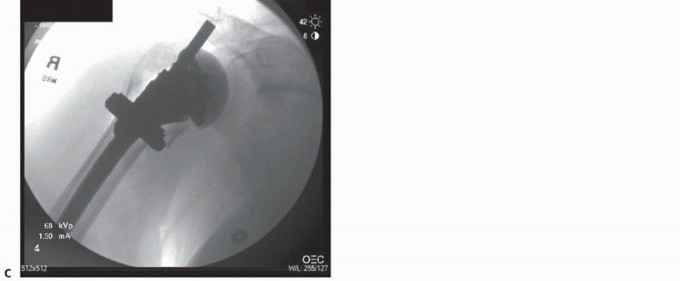

Illustration 5 for Hemiarthroplasty for Proximal: Effective Treatment for Fractures --- Illustration 6 for Hemiarthroplasty for Proximal: Effective Treatment for Fractures Illustration 7 for Hemiarthroplasty for Proximal: Effective Treatment for Fractures Illustration 8 for Hemiarthroplasty for Proximal: Effective Treatment for Fractures ### FIG 3 • A,B. Fracture-specific stem with commercially available fracture jig allows for intraoperative trial reduction. (A: Courtesy of Depuy-Synthes, Warsaw, IN; B: Copyright Kamal I. Bohsali, MD.) Endotracheal intubation is recommended to allow for intraoperative muscle relaxation, but laryngeal mask intubation may be used.12,14 ## Positioning The patient is placed on an operating table in the beachchair position with the arm positioned in a sterile articulating arm holder or draped free if an appropriate number of assistants are available (FIG 4). Intraoperative C-arm fluoroscopy is recommended and will assist the surgeon in implant placement and tuberosity positioning. Illustration 9 for Hemiarthroplasty for Proximal: Effective Treatment for Fractures --- Illustration 10 for Hemiarthroplasty for Proximal: Effective Treatment for Fractures ### FIG 4 • A,B. The patient is placed on an operating table in the beach-chair position, with the arm positioned in a sterile articulating arm holder or draped free with use of a padded Mayo stand. (Copyright Kamal I. Bohsali, MD.)

Indications 1. A complete history and physical examination should be performed, with particular attention paid to the neurovascular status. Imaging studies 1. Appropriate plain radiographs with possible CT scan supplementation aid in the surgical decision making. C-arm fluoroscopy is useful for intraoperative implant and tuberosity positioning. Tuberosity identification Use the long head of the biceps to define the tuberosities for mobilization. Tag this for later tenodesis before wound closure. Implant placement Know the specifics of the implant system including its limitations. Place the implant in appropriate retroversion (approximately 20-30 degrees). Check the height of the trial stem before performing cement fixation using a fracture jig or sponge for provisional fixation. Intraoperative fluoroscopy can be used to assess appropriate implant height. Tuberosity fixation 1. Avoid loss of external rotation or internal rotation with overreduction of the lesser and greater tuberosities, respectively. Postoperative ▪ On postoperative day 1, initiate gentle pendulum exercises, with passive rehabilitation forward flexion and external rotation (at 0 degrees of abduction). Always modify rehabilitation protocol based on intraoperative assessment of soft tissue compromise and patient neurologic status. ## POSTOPERATIVE CARE Physician-directed therapy is initiated on postoperative day 1 with gentle, gravity-assisted pendulum exercises, as well as passive pulley-and-stick exercises to maintain forward flexion and external rotation (motion limits placed by surgeon based on intraoperative stability). After discharge, the patient's wound is reexamined and sutures removed at 10 to 14 days. Gentle range-of-motion exercises are continued. At 6 weeks, repeat radiographs are obtained to evaluate tuberosity healing. When tuberosity healing is evident, phase 2 exercises are initiated with isometric rotator cuff exercises and active-assisted elevation with the pulley. At 3 months, strength training with graduated rubber bands (phase 3) is implemented. Maximal motion and function are obtained at about 12 months from date of surgery. ## OUTCOMES About 90% of patients treated with hemiarthroplasty demonstrate minimal pain, despite a wide range of function, motion, and strength. Factors that portend a poor outcome after hemiarthroplasty for fractures include tuberosity malposition, superior migration of the humeral prosthesis, stiffness, persistent pain, poor initial positioning of the implant (excessive retroversion, decreased height), and age older than 75 years in women.4,5,27 When comparing acute intervention versus late reconstruction, most authors report poorer outcomes with delayed surgical intervention (more than 2 weeks), particularly with functional results.22,29 ## COMPLICATIONS Complications include delays in wound healing, infection, nerve injury, humeral fracture, component malposition, instability, nonunion of the tuberosities, rotator cuff tearing, regional pain syndrome, periarticular fibrosis, heterotopic bone formation, component loosening, and glenoid arthritis.3,7,21 The most common problems in acute fracture treatment involve stiffness, nonunion, malunion, or resorption of the tuberosities.7,21 In patients with chronic fractures treated with hemiarthroplasty, the most common problems encountered were instability, heterotopic ossification, tuberosity malunion or nonunion, and rotator cuff tears.21 ##